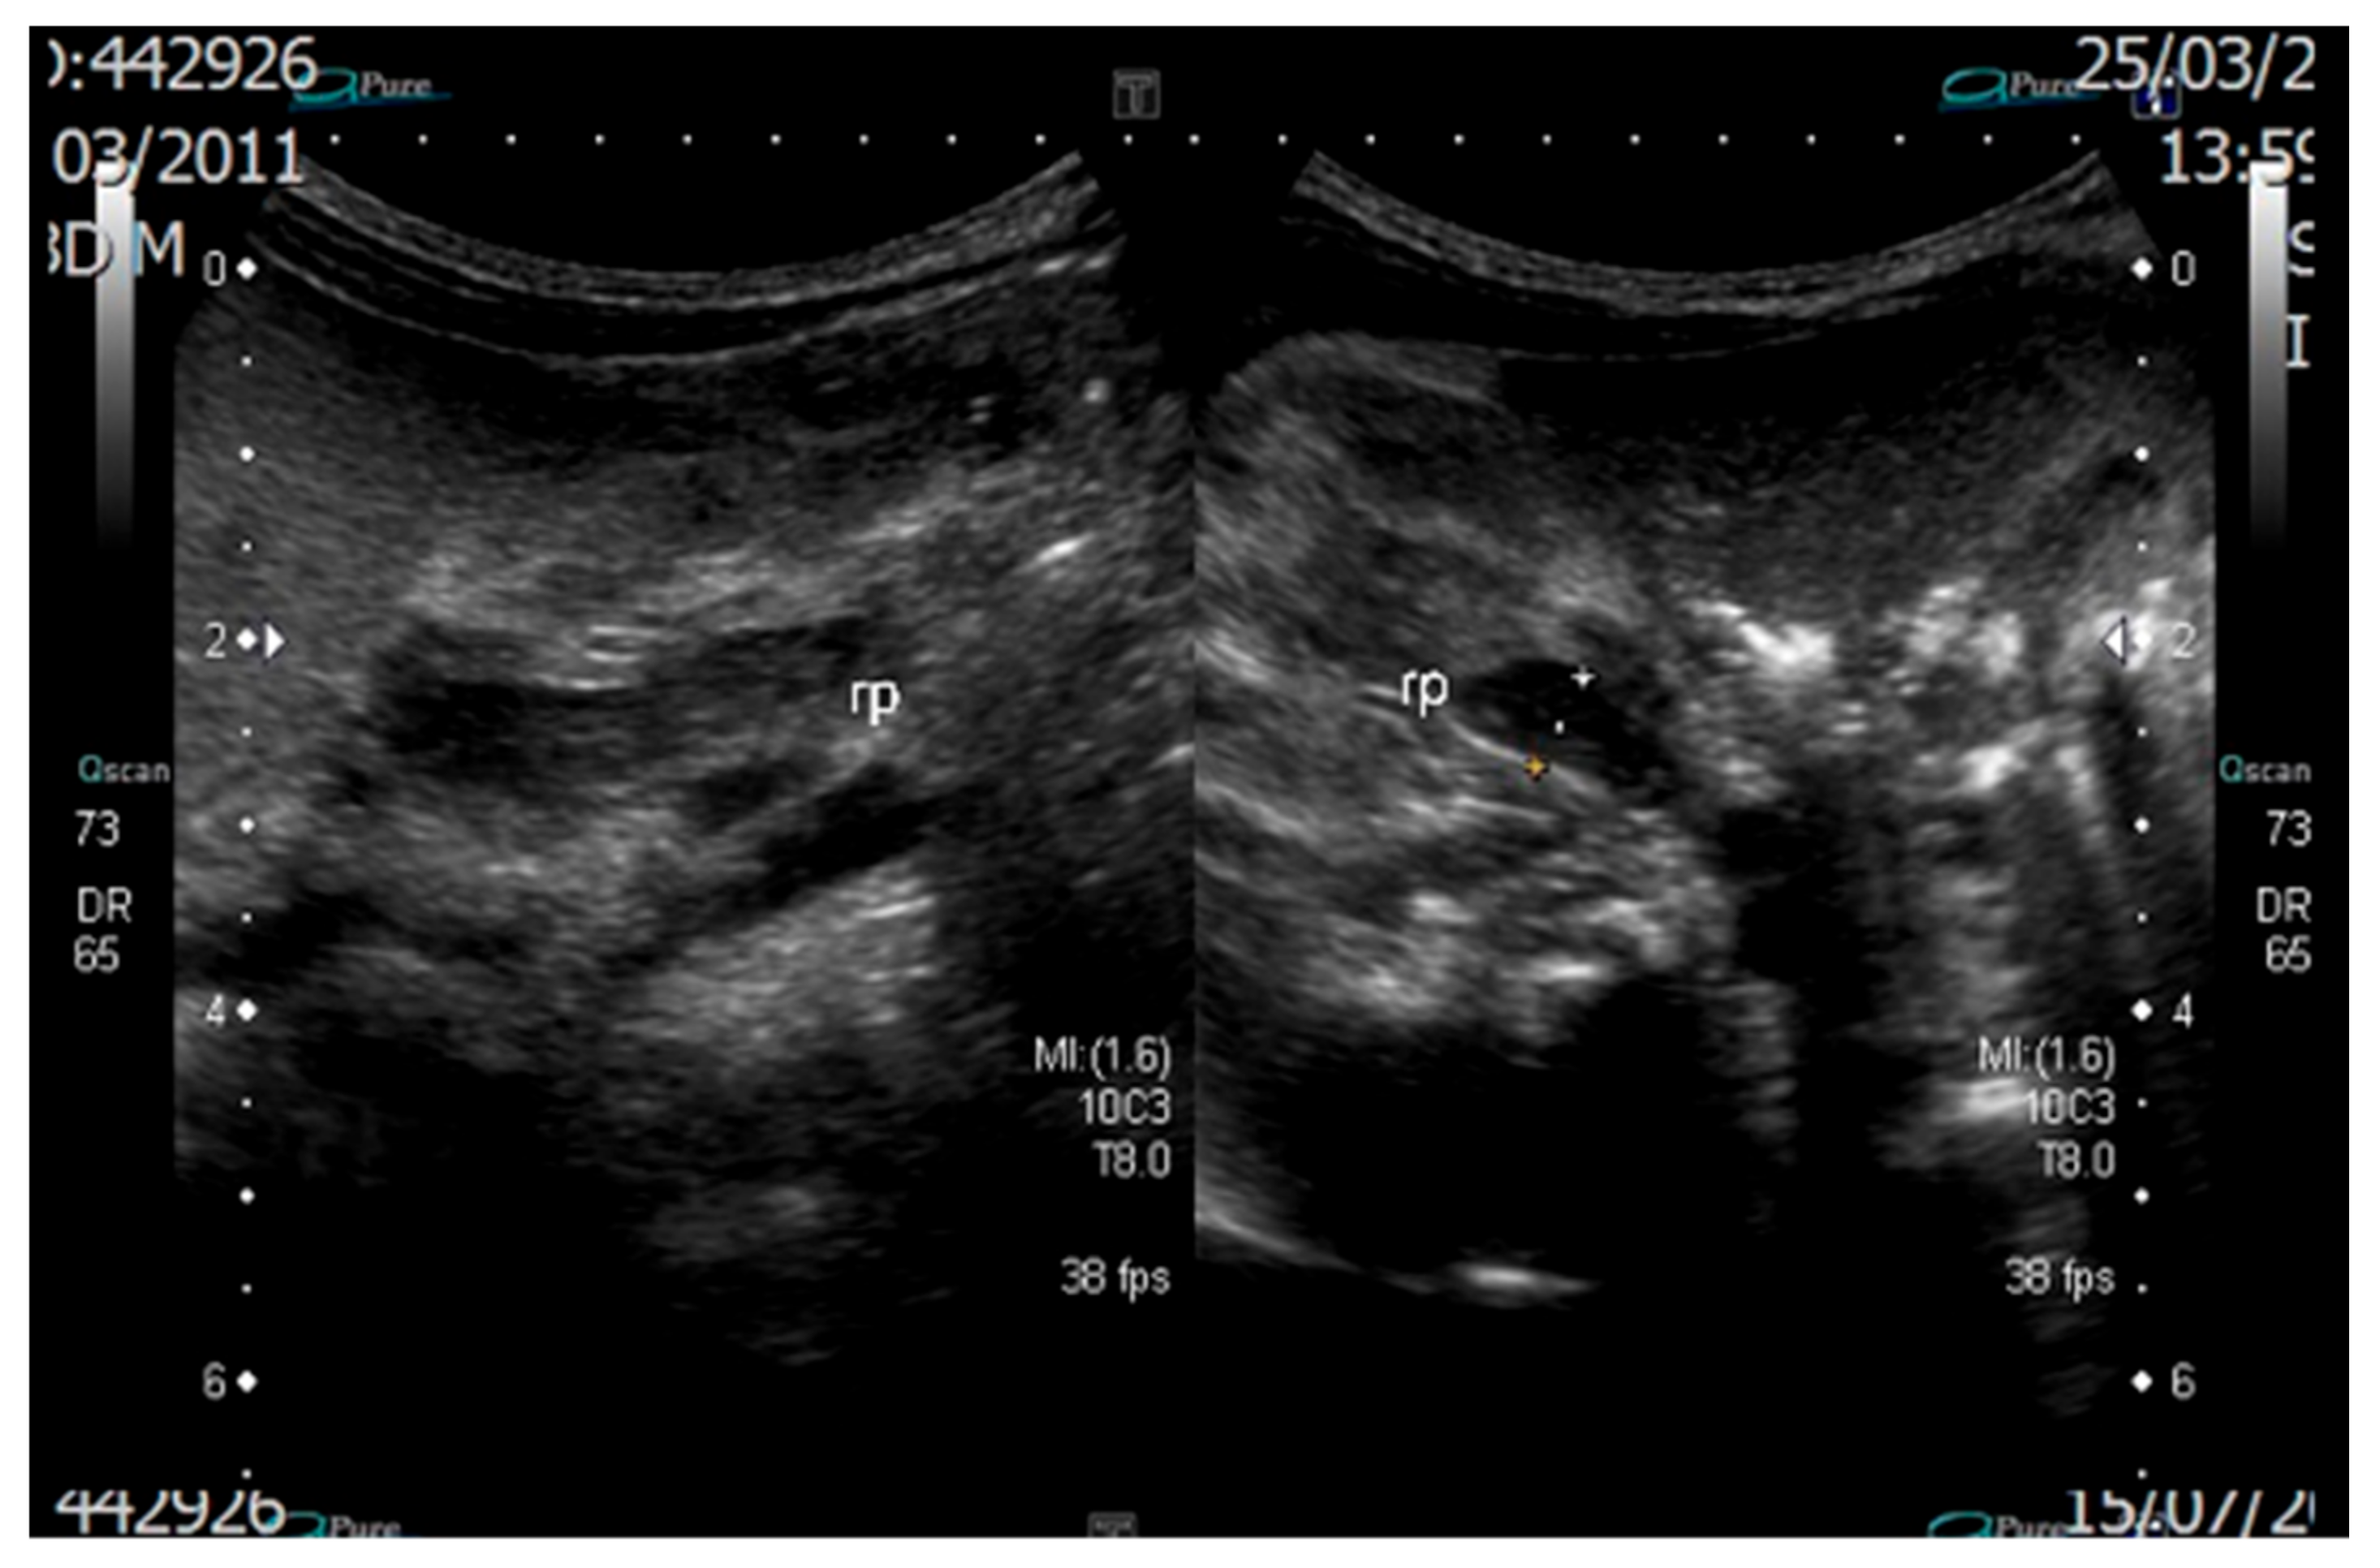

2. Case Report